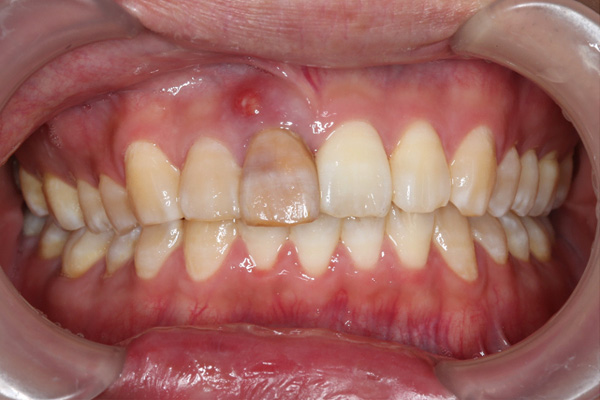

BEFORE

AFTER

| 年代・性別 | 30代 男性 |

|---|---|

| 主訴 | 前歯が腫れた |

| 治療期間 | 約18ヶ月 |

| 費用 | 700,000円 |

| 治療内容 | インプラント、部分矯正、骨造成、結合組織移植、セラミック修復 |

| 治療に伴うリスク | インプラント周囲炎 セラミックの破折、脱離 |